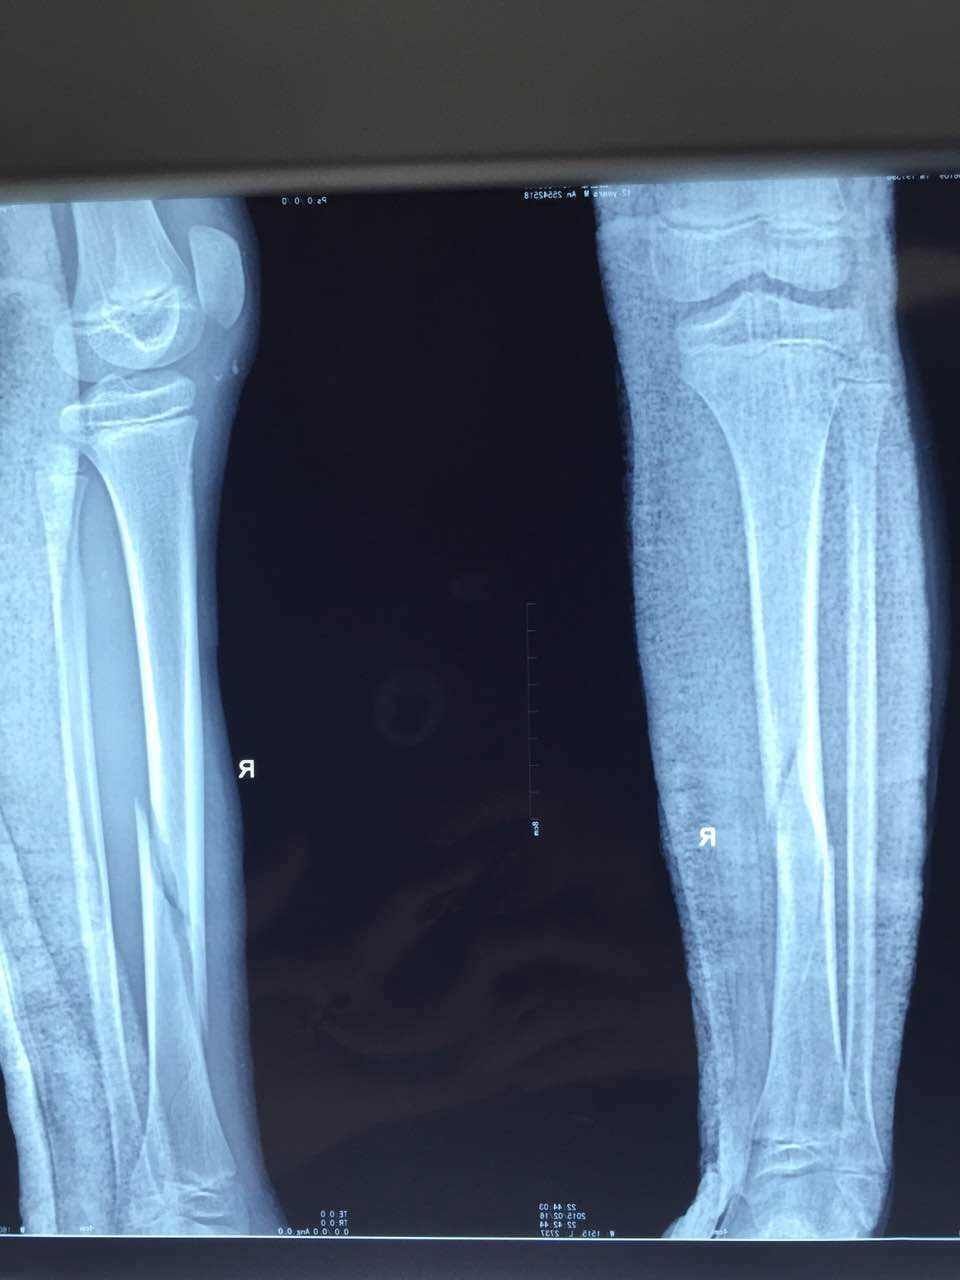

热烈祝贺中山马新医院又一例粉碎性骨折手术圆满成功!

粉碎性骨折属于完全性骨折,指骨质碎裂成三块以上,股骨部位粉碎性骨折会使人变成瘸子。骨折部有局限性疼痛和压痛,局部肿胀和出现瘀斑,肢体功能部位或完全丧失,完全性骨折尚可出现肢体畸形及异常活动。